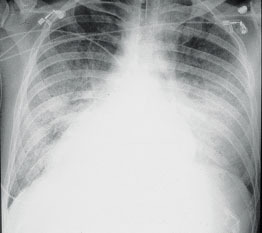

Pneumonia is one of the most common of lung infections among the elderly but concerns of underlying conditions arise when it recurs, a leading South African pulmonologist said Sunday.

Nelson Mandela was admitted Saturday in a "serious but stable" condition for a recurrent lung infection.

It is his fourth hospital stay since December and his third for lung infection. The Nobel peace prize laureate, who turns 95 next month, was in April hospitalized for 10 days for pneumonia treatment. Officials have not specified if the latest infection afflicting Mandela is pneumonia.

Of the different types of lung infections, "pneumonia is the most serious and the most common in elderly patients," said professor Guy Richards, director of critical care at Johannesburg's Charlotte Maxeke Academic Hospital.